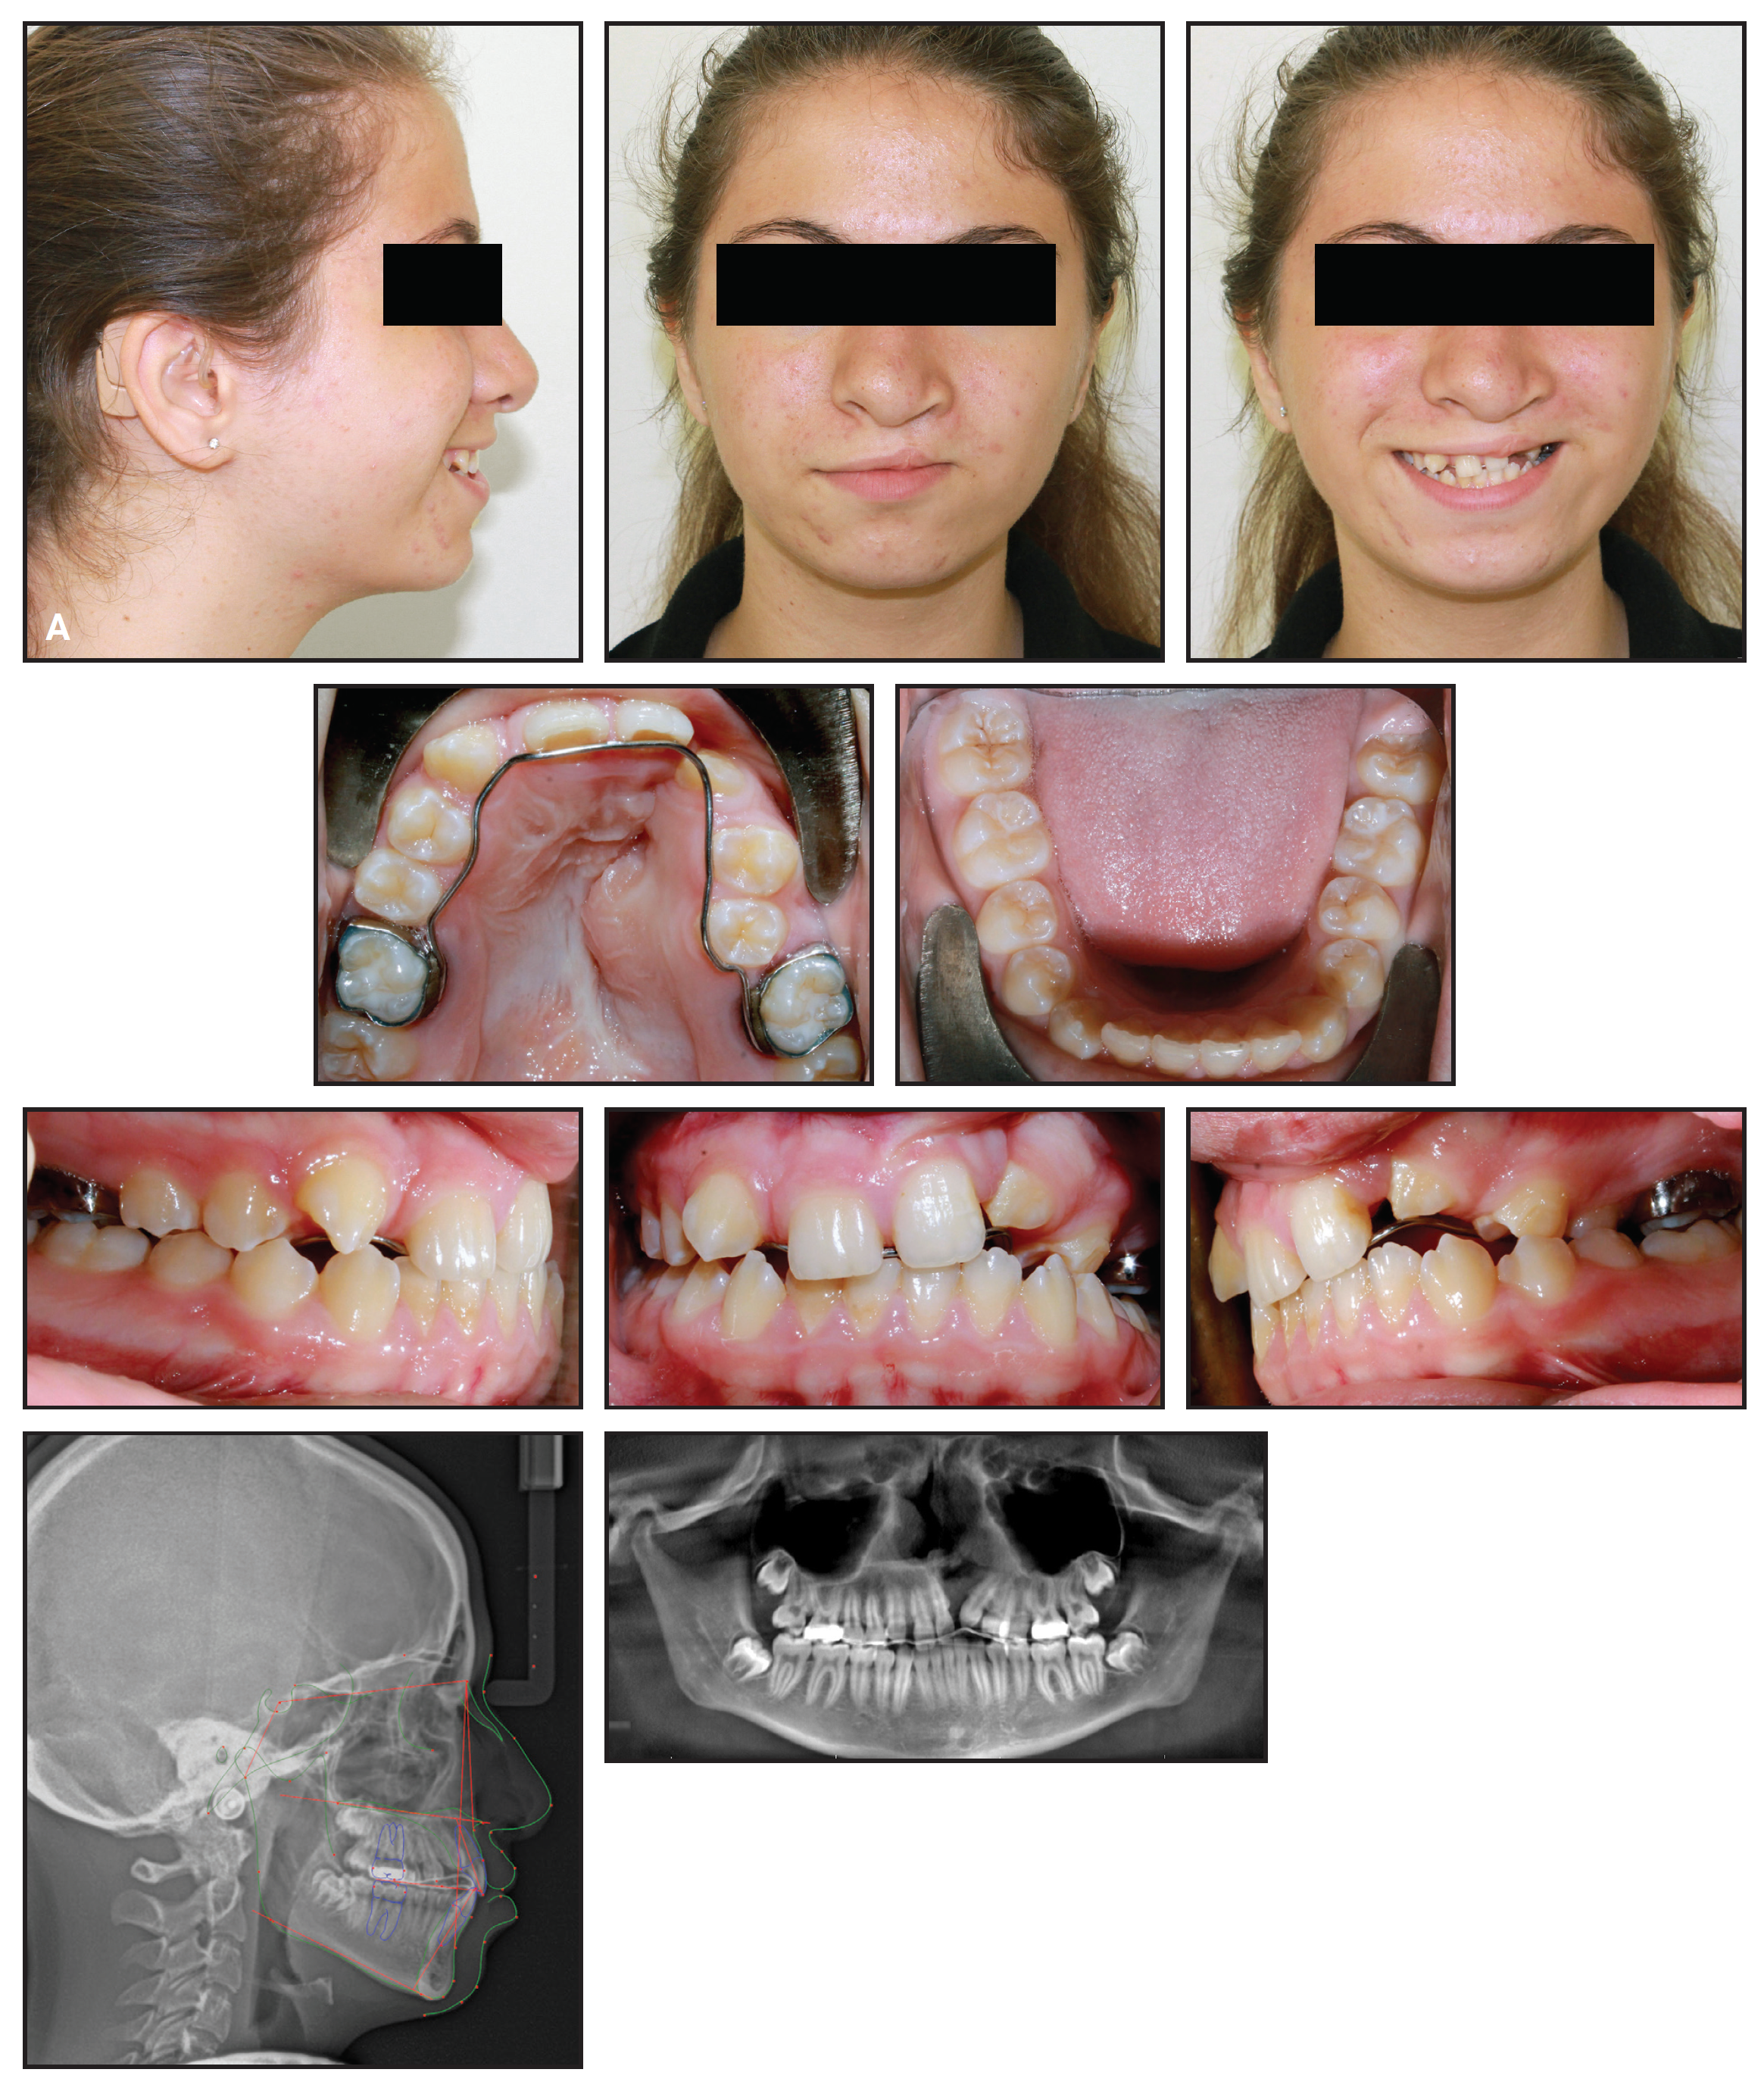

February 2026 Issue HighlightsOVERVIEWBiomechanical Principles and Techniques for Management of Maxillary and Mandibular Second MolarsThe authors review orthodontic biomechanics used to control maxillary and mandibular second molars during comprehensive treatment. Emphasis is placed on anchorage considerations, torque control, bite-opening strategies, and clinical techniques for managing erupted, partially erupted, or impacted second molars.